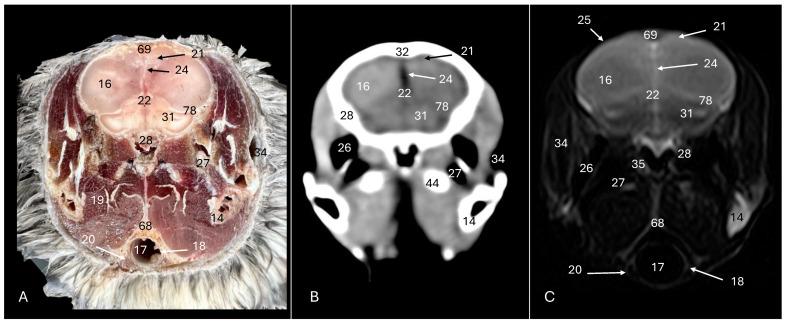

科里氏剪水鹱(:通过横断面解剖、计算机断层扫描和磁共振成像探索正常头部解剖结构。

Cory's Shearwater (): Exploring Normal Head Anatomy through Cross-Sectional Anatomy, Computed Tomography and Magnetic Resonance Imaging.

Cory's shearwater, or , stands out as a symbolic figure in the world of seabirds, playing a crucial role in marine ecosystems globally. Belonging to the Procellariidae family, it is singularized by its imposing wingspan and intricate migration patterns connecting it to various regions from the North Atlantic to the Pacific. Its role in the marine food chain, specialized diet and adaptation for nesting in the Canary Archipelago underscore its ecological importance. However, Cory's shearwater also faces important threats, such as the invasion of foreign species, highlighting the need for its conservation. Among the conservation issues, studies on its biology, the main threats it faces and its normal anatomy are essential to preserve marine biodiversity. Additionally, a variety of imaging techniques, such as computed tomography and magnetic resonance, facilitates the understanding of the bird's neuroanatomy and opens future research possibilities in comparative neuroscience. Moreover, this approach proves particularly relevant given the increasing attention these seabirds receive in environments such as zoos, rehabilitation centers and their natural habitat, where veterinarians play a crucial role in their care and well-being.

摘要

科里氏剪水鹱,或称[具体名称],在海鸟世界中是一个具有象征意义的物种,在全球海洋生态系统中发挥着关键作用。它属于鹱科,其显著特征是翼展巨大,以及有着复杂的迁徙模式,使其与从北大西洋到太平洋的各个地区相连。它在海洋食物链中的作用、特殊的饮食习性以及在加那利群岛筑巢的适应性,都凸显了其生态重要性。然而,科里氏剪水鹱也面临着重大威胁,比如外来物种的入侵,这凸显了对其进行保护的必要性。在保护问题中,对其生物学、面临的主要威胁以及正常解剖结构的研究对于保护海洋生物多样性至关重要。此外,诸如计算机断层扫描和磁共振等多种成像技术,有助于了解该鸟类的神经解剖结构,并为比较神经科学开启未来的研究可能性。而且,鉴于这些海鸟在动物园、康复中心及其自然栖息地等环境中受到越来越多的关注,这种方法被证明尤为重要,在这些环境中,兽医在它们的护理和健康方面发挥着关键作用。